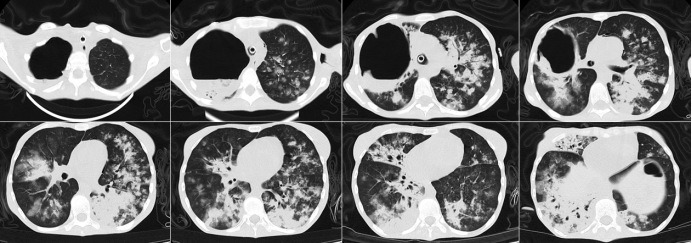

当地医院行支气管镜检查,见双侧多叶段支气管大量土黄色黏稠分泌物,支气管肺泡灌洗液(BALF)真菌培养提示黑曲霉,细胞分类显示中性粒细胞占93.5%,巨噬细胞4%;予伏立康唑抗真菌治疗。但治疗1个月后,患者病情进行性加重,2024年1月12日复查胸部CT显示双肺多发斑片实变影,右肺上叶巨大空洞,内见气液平面,较前进展(图2)。遂转入中日医院进一步治疗。

图2 复查胸部CT(2024-01-12)